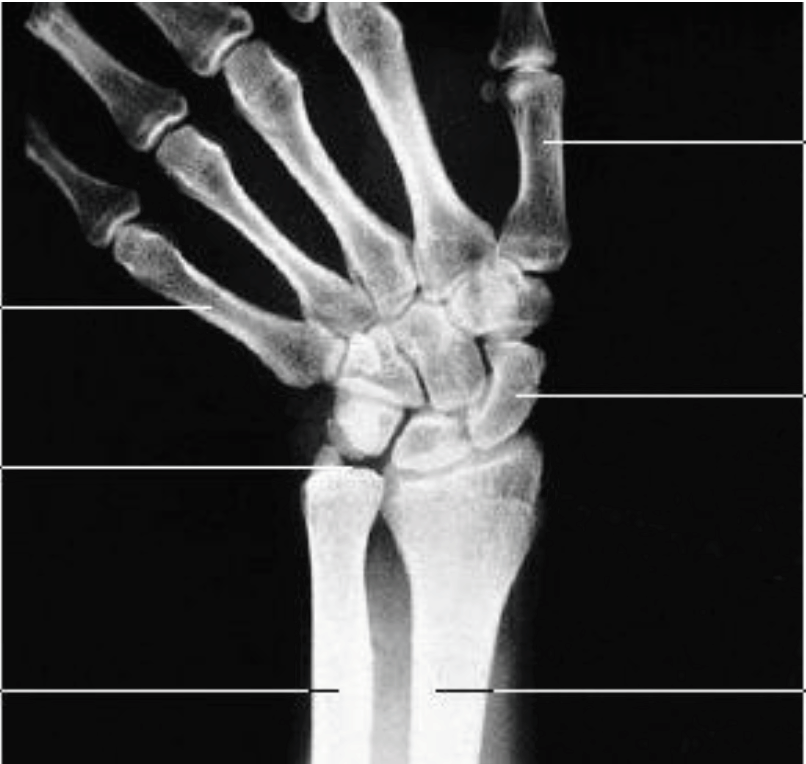

What is this view of the hand? What views are missing?

Scaphoid

MISSING:

PA

Lateral

Lateral Oblique (PA)

Medial Oblique (PA)